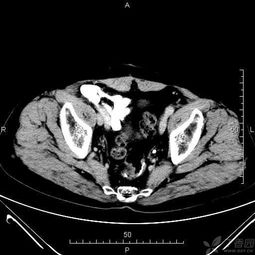

一,檢查前病人禁食即可.二.腹部檢查之前不能做其它造影檢查,尤其不能用鋇劑行消化道造影,以免腸內殘留的造影劑形成偽影,影響ct圖像質(zhì)量,從而導致誤診.

各部位增強掃描及腹部平掃者,檢查前至少禁食四小時(shí).

腹部檢查者,檢查前三日內不食重金屬類(lèi)物及不作鋇餐檢查.

需增強掃描者,檢查前需禁食一餐且三日內不食重金屬類(lèi)物及不作鋇餐檢查.

增強掃描病人,可能會(huì )出現過(guò)敏反應等癥狀.

嚴重肝,腎功能損害及嚴重過(guò)敏體質(zhì)者應慎用造影劑.